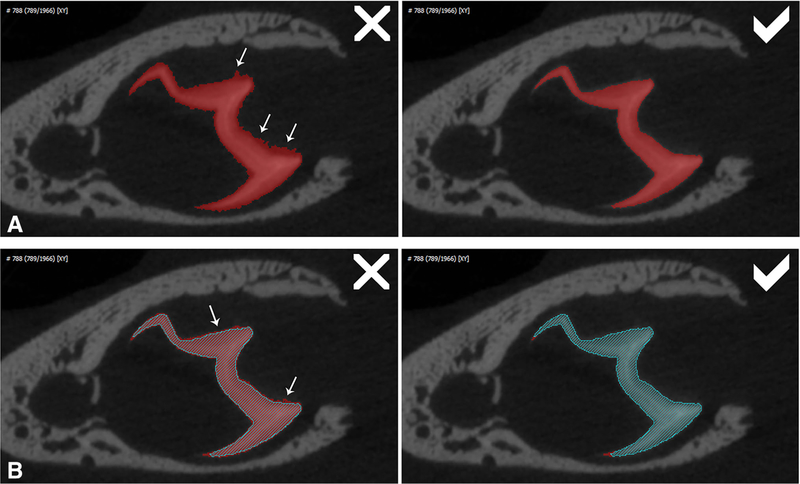

Description:Previous descriptive work on deciduous dentition of primates has focused disproportionately on great apes and humans. To address this bias in the literature, we studied 131 subadult nonhominoid specimens (including 110 newborns) describing deciduous tooth morphology and assessing maximum hydroxyapatite density (MHD). All specimens were CT scanned at 70 kVp and reconstructed at 20.5-39 μm voxels. Grayscale intensity from scans was converted to hydroxyapatite (HA) density (mg HA/cm| ) using a linear conversion of grayscale values to calibration standards of known HA density (R| = .99). Using Amira software, mineralized dental tissues were captured by segmenting the tooth cusps first and then capturing the remainder of the teeth at descending thresholds of gray levels. We assessed the relationship of MHD of selected teeth to cranial length using Pearson correlation coefficients. In monkeys, anterior teeth are more mineralized than postcanine teeth. In tarsiers and most lemurs and lorises, postcanine teeth are the most highly mineralized. This suggests that monkeys have a more prolonged process of dental mineralization that begins with incisors and canines, while mineralization of postcanine teeth is delayed. This may in part be a result of relatively late weaning in most anthropoid primates. Results also reveal that in lemurs and lorises, MHD of the mandibular first permanent molar (M| ) negatively correlates with cranial length. In contrast, the MHD of M| positively correlates with cranial length in monkeys. This supports the hypothesis that natural selection acts independently on dental growth as opposed to mineralization and indicates clear phylogenetic differences among primates.